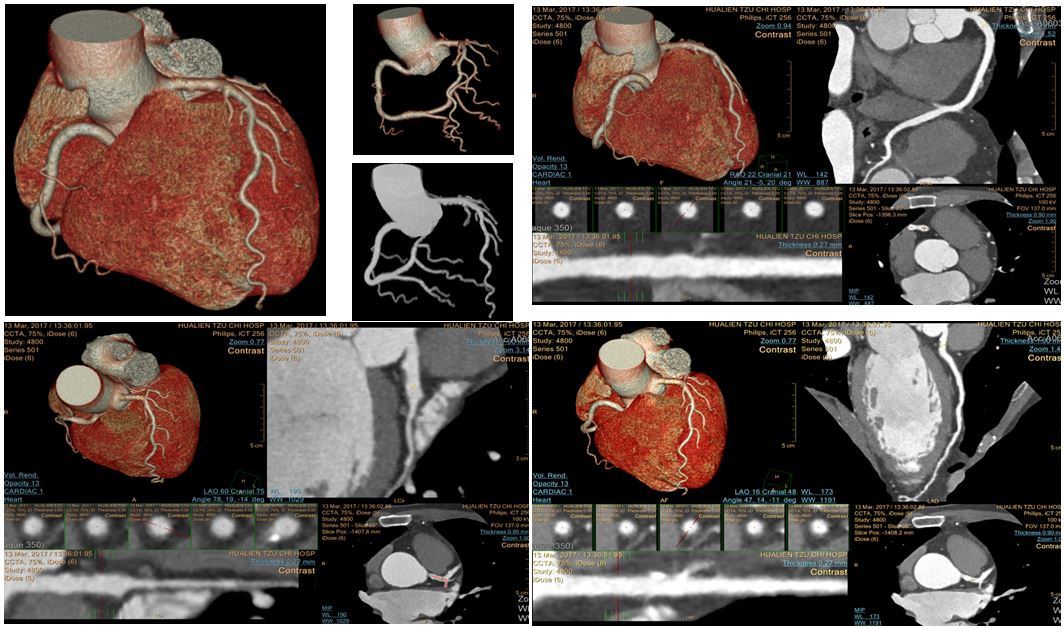

1. 電腦斷層心臟冠狀動脈血管攝影 (CCTA:Coronary computed tomography angiography)

本部於109年12月引進最新的電腦斷層掃描儀512 slices MDCT(512 RCT, GE),藉由螺旋式連續掃描於一次閉氣時間取得三維心臟血管的影像資料,再經由電腦的成像技術及軟體重組分析,可檢測血管的異常、如廔管、狹窄、鈣化…等。

其適應症如下﹕

- 無症狀但為心肌梗塞高危險,例如﹕高血壓、糖尿病、高血脂、抽煙、有家族。

- 有症狀需評估冠狀動脈狹窄者,非典型心絞痛的患者、運動心電圖異常的患者、懷疑冠狀動脈異常的患者,先天性心臟病患者或已知有冠狀動脈狹疾病者。

- 冠狀動脈繞道手術術後追蹤,評估支架(>3mm)通暢與否。

該檢查比傳統介入性的血管攝影檢查傷害小,不需住院,引起之不適較少,解除病患對於侵入性心導管檢查的畏懼感。